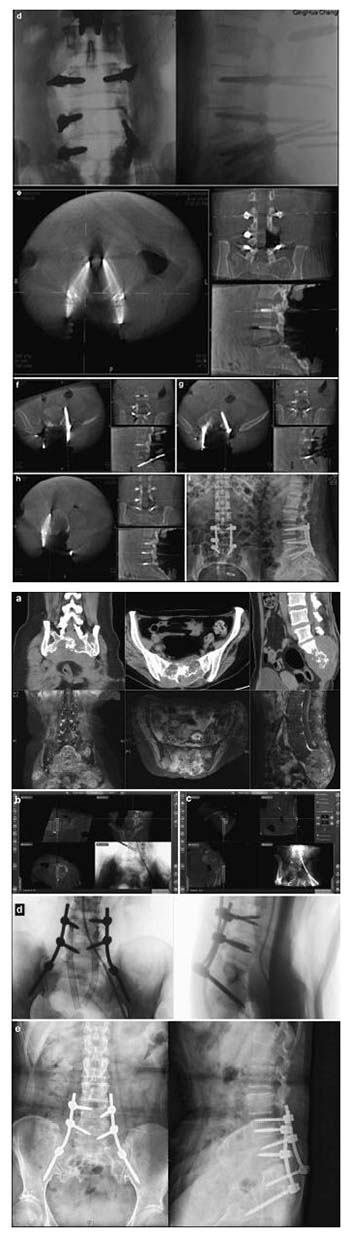

20171023161407 Figure 4 Preoperative, intraoperative, and postoperative images of patients in the nearly total sacrococcygeal chordoma resection and pedicle screw fixation group. (a) Lumbosacral vertebral computed tomography shows an S1-3 intraspinal isodense tumor and a severely damaged vertebral body. An enhanced magnetic resonance imaging scan shows S1-3 intraspinal internal and external tumors and a vertebral body that has been invaded and damaged. (b) Intraoperative L4 left pedicle screw implantation is performed under navigation. The direction, angle, and depth of the screw entery can be seen to match the navigation plan. (c) Intraoperative right iliac screw implantation is conducted under navigation. The direction, angle, and depth of the screw entering can be seen according to the navigation plan. (d) After screw implantation, an O-arm two-dimensional lateral scan shows good screw positioning. (e) A lateral lumbar radiographic scan, 7 days postoperatively, shows firm pedicle and iliac screw fixation and good positioning.

20171023161447 Figure 5 Preoperative, intraoperative, and postoperative images of patients in the percutaneous minimally invasive pedicle internal fixation group. (a) Lumbosacral vertebral computed tomography shows L3 vertebral spondylolisthesis, L3-4 and L4-5 spinal stenosis, intervertebral disc degeneration, and corresponding intervertebral space narrowing. (b) Intraoperative L4 right pedicle screw implantation is performed under navigation. The direction, angle, and depth of screw entry can be seen in real-time, according to the navigation plan. (c, d) Intraoperative screw implantation and bar threading are performed under navigation. (e, f) After screw implantation, O-arm three-dimensional anteroposterior and lateral scans show that the screw is well positioned.